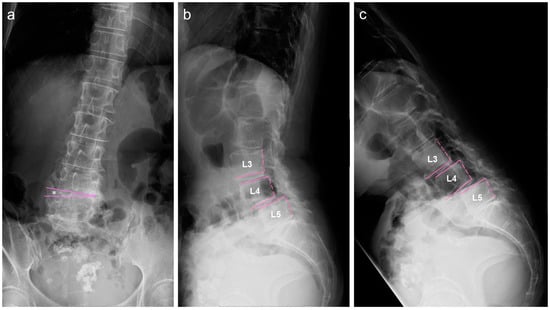

2.2. Image Examinations at First Visit

2.4. Image Examinations after Six Months of Daily Physical Exercise